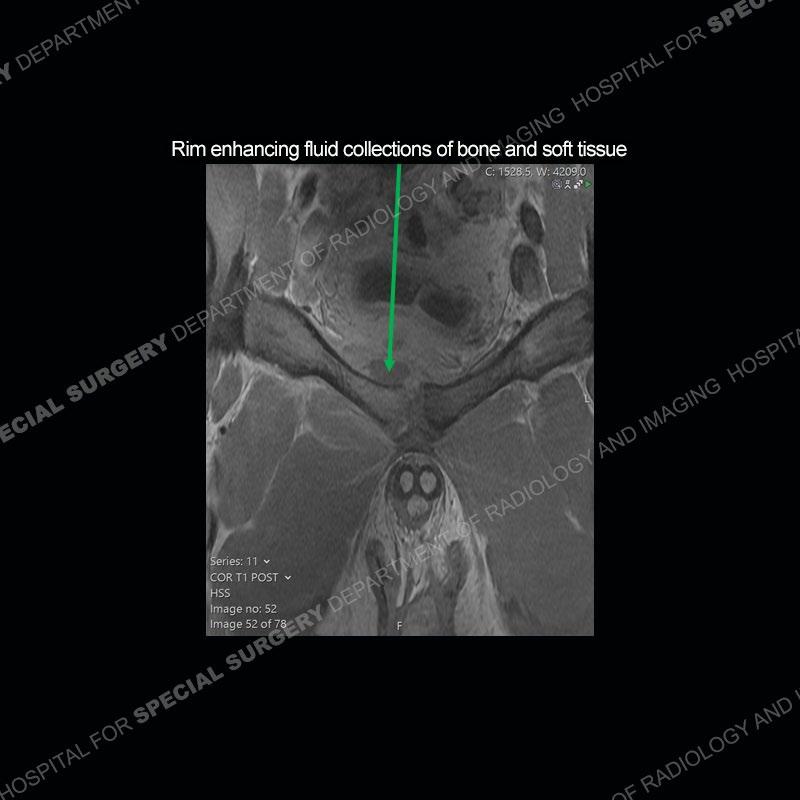

Subsequent MRI in a very short time interval shows markedly increased abnormality of the ramus and increased edema and “mass” of the soft tissue. Post contrast imaging shows multiple, rim enhancing collections of the soft tissue and similar albeit less conspicuous enhancing collection of the ramus.

The repeat MRI, with the marked degree of increased abnormality of the bone and soft tissue shifted the diagnosis to a high degree towards infection. Even the most aggressive of neoplasms would not have that the degree of change in a 3-day time span. The CT study was shown before the repeat MRI but actually occurred just after the repeat MRI. It helped confirm the destructive process of the ramus and particularly the abnormal architecture along the inferior margin. The patient went on to have a CT guided aspiration of one of the soft tissue collections with 4cc of purulent fluid obtained. A surgical irrigation and debridement of the bone and soft tissue was performed. A PICC line was placed and the patient is currently undergoing IV antibiotic treatment with a possible repeat irrigation and debridement.